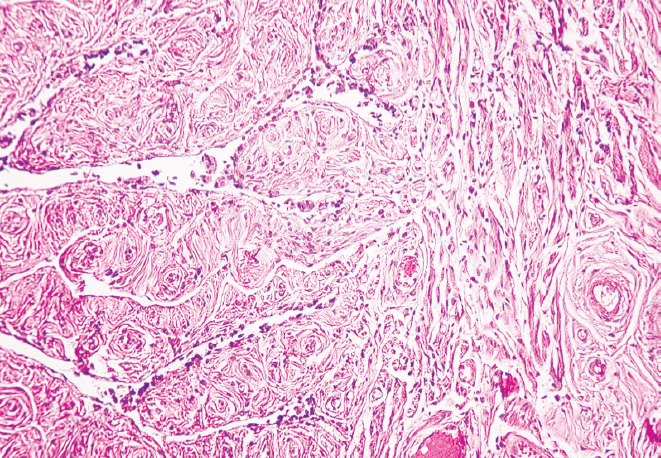

Перешеек и воронка маточных труб женщин старческого возраста характеризуются наличием утолщенных складок слизистой оболочки и уплощенным эпителием. Наблюдается неравномерное сужение просвета как в перешейке, так и в воронке, обусловленное близким друг к другу расположением складок слизистой оболочки, частично объединенных между собой. В старческом возрасте циркулярный и продольный слои мышечной оболочки выглядят истонченными в сравнении с образцами, взятыми для исследования у женщин молодого возраста. Наряду с этим у женщин старческого возраста выявлено разрастание соединительной ткани в стенке маточной трубы как в области воронки, так и в области перешейка. Видны скопления адипоцитов, локализующихся в подсерозной основе, где сосуды в утолщенной стенке располагаются группами (рис. 3, 4).

Рис. 4. Фрагмент воронки маточной трубы женщины в возрасте 86 лет. Окраска гематоксилином и эозином, увел. ×10